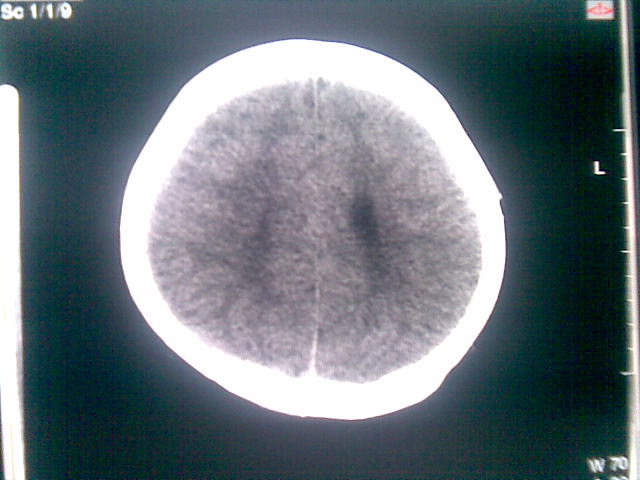

以下是引用随光逐影在2010-1-5 16:32:00的发言:[br]1)鞍上池囊性占位性病变,不排除蛛网膜囊肿可能;建议行mri检查。2)脑积水。

以下是引用yangyang2000在2010-1-5 20:41:00的发言:[br])鞍上池囊性占位性病变,不排除蛛网膜囊肿可能;建议行mri检查。2)脑积水

以下是引用yangyudong333在2010-1-5 21:28:00的发言:[br]1)鞍上池囊性占位性病变,不排除蛛网膜囊肿可能;建议行mri检查。2)脑积水。